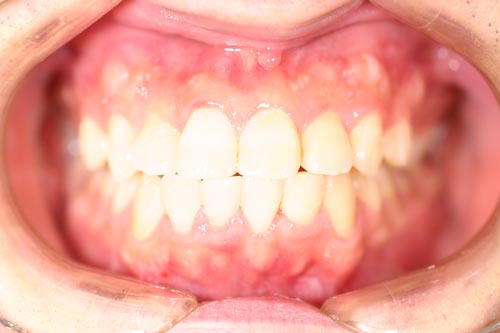

上顎の中央の歯一本が前にとびだしている治療例

Before

After

上顎の中央の歯一本が前にとびだしている症例です。これだけ前に出ていると、歯を抜いて並べていくか、何本かの歯を削らないときれいに並べられません。

このケースは、上の顎に矯正用のミニスクリュー{矯正用ミニインプラント}を入れて、歯を抜かず、削りもしないで、しかも上顎だけの矯正で治した症例です。

矯正用インプラントを使うことによって歯並び全体を後方に動かすことができるようになったため、このような治療ができるようになりました。

年齢 20代

治療期間 8ヶ月

治療費用 800,000円

治療のリスク 特になし